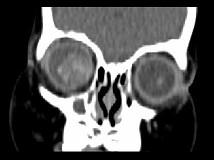

问题 男,2岁、右眼白瞳症1个月,CT影像如图,最可能的诊断为()

选项 A.眼球内寄生虫病 B.永存原始玻璃体增生症 C.脉络膜骨病 D.Coats病 E.视网膜母细胞瘤

答案 E